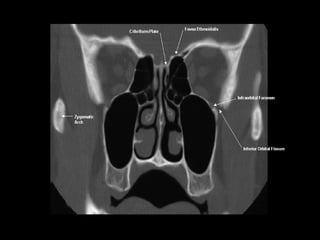

Radiographers use medical imaging equipment like X-rays and MRIs to produce images of patients' internal structures and organs. They are responsible for positioning patients, operating scanning machines, and ensuring quality images. Radiographers must have strong attention to detail, excellent communication skills, and the ability to work well under pressure to accurately capture anatomical features and diagnose any abnormalities.